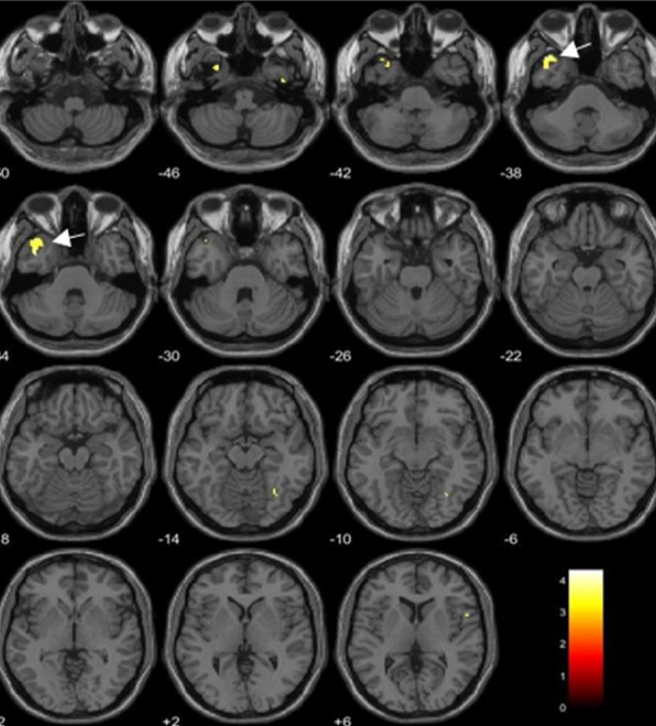

VBM(voxel based morphometry)

脳全体をボクセルベースで組織分類し統計的手法を用いて脳の体積や構造の変化を測定評価する解析技術です。​

VBMは神経科学や臨床研究において疾患や障害と関連する脳の構造的な変化の特定に用いられています。​

また、fMRIやPET(positron emission tomography)などと合わせて脳機能と脳構造の関係を理解するために用いられることもあります。

咀嚼運動に対する海馬体積の変化を評価しています(日本大学松戸歯学部とBioViewの共同研究)。​

(ヒト (n=6) の グループ解析結果)​

ダイオキシンの血中濃度と脳体積の相関について評価しています。

有意な負の相関を示す脳領域(p < 0.05でFDR補正)を黄色と矢印で示しています。

左:ダイオキシン類の1つであるTCDDの血中濃度と脳体積の相関を評価

右:ダイオキシン類の1つであるPCDDの毒性を1としたときの毒性当量(TEQ-PCDD)の血中濃度と脳体積の相関を評価

Alterations in Regional Alterations in Regional Brain Regional Volume Associated with Dioxin Exposure in Men Living in the Most Dioxin-Contaminated Area in Vietnam: Magnetic Resonance Imaging (MRI) Analysis Using Voxel-Based Morphometry (VBM) より引用​